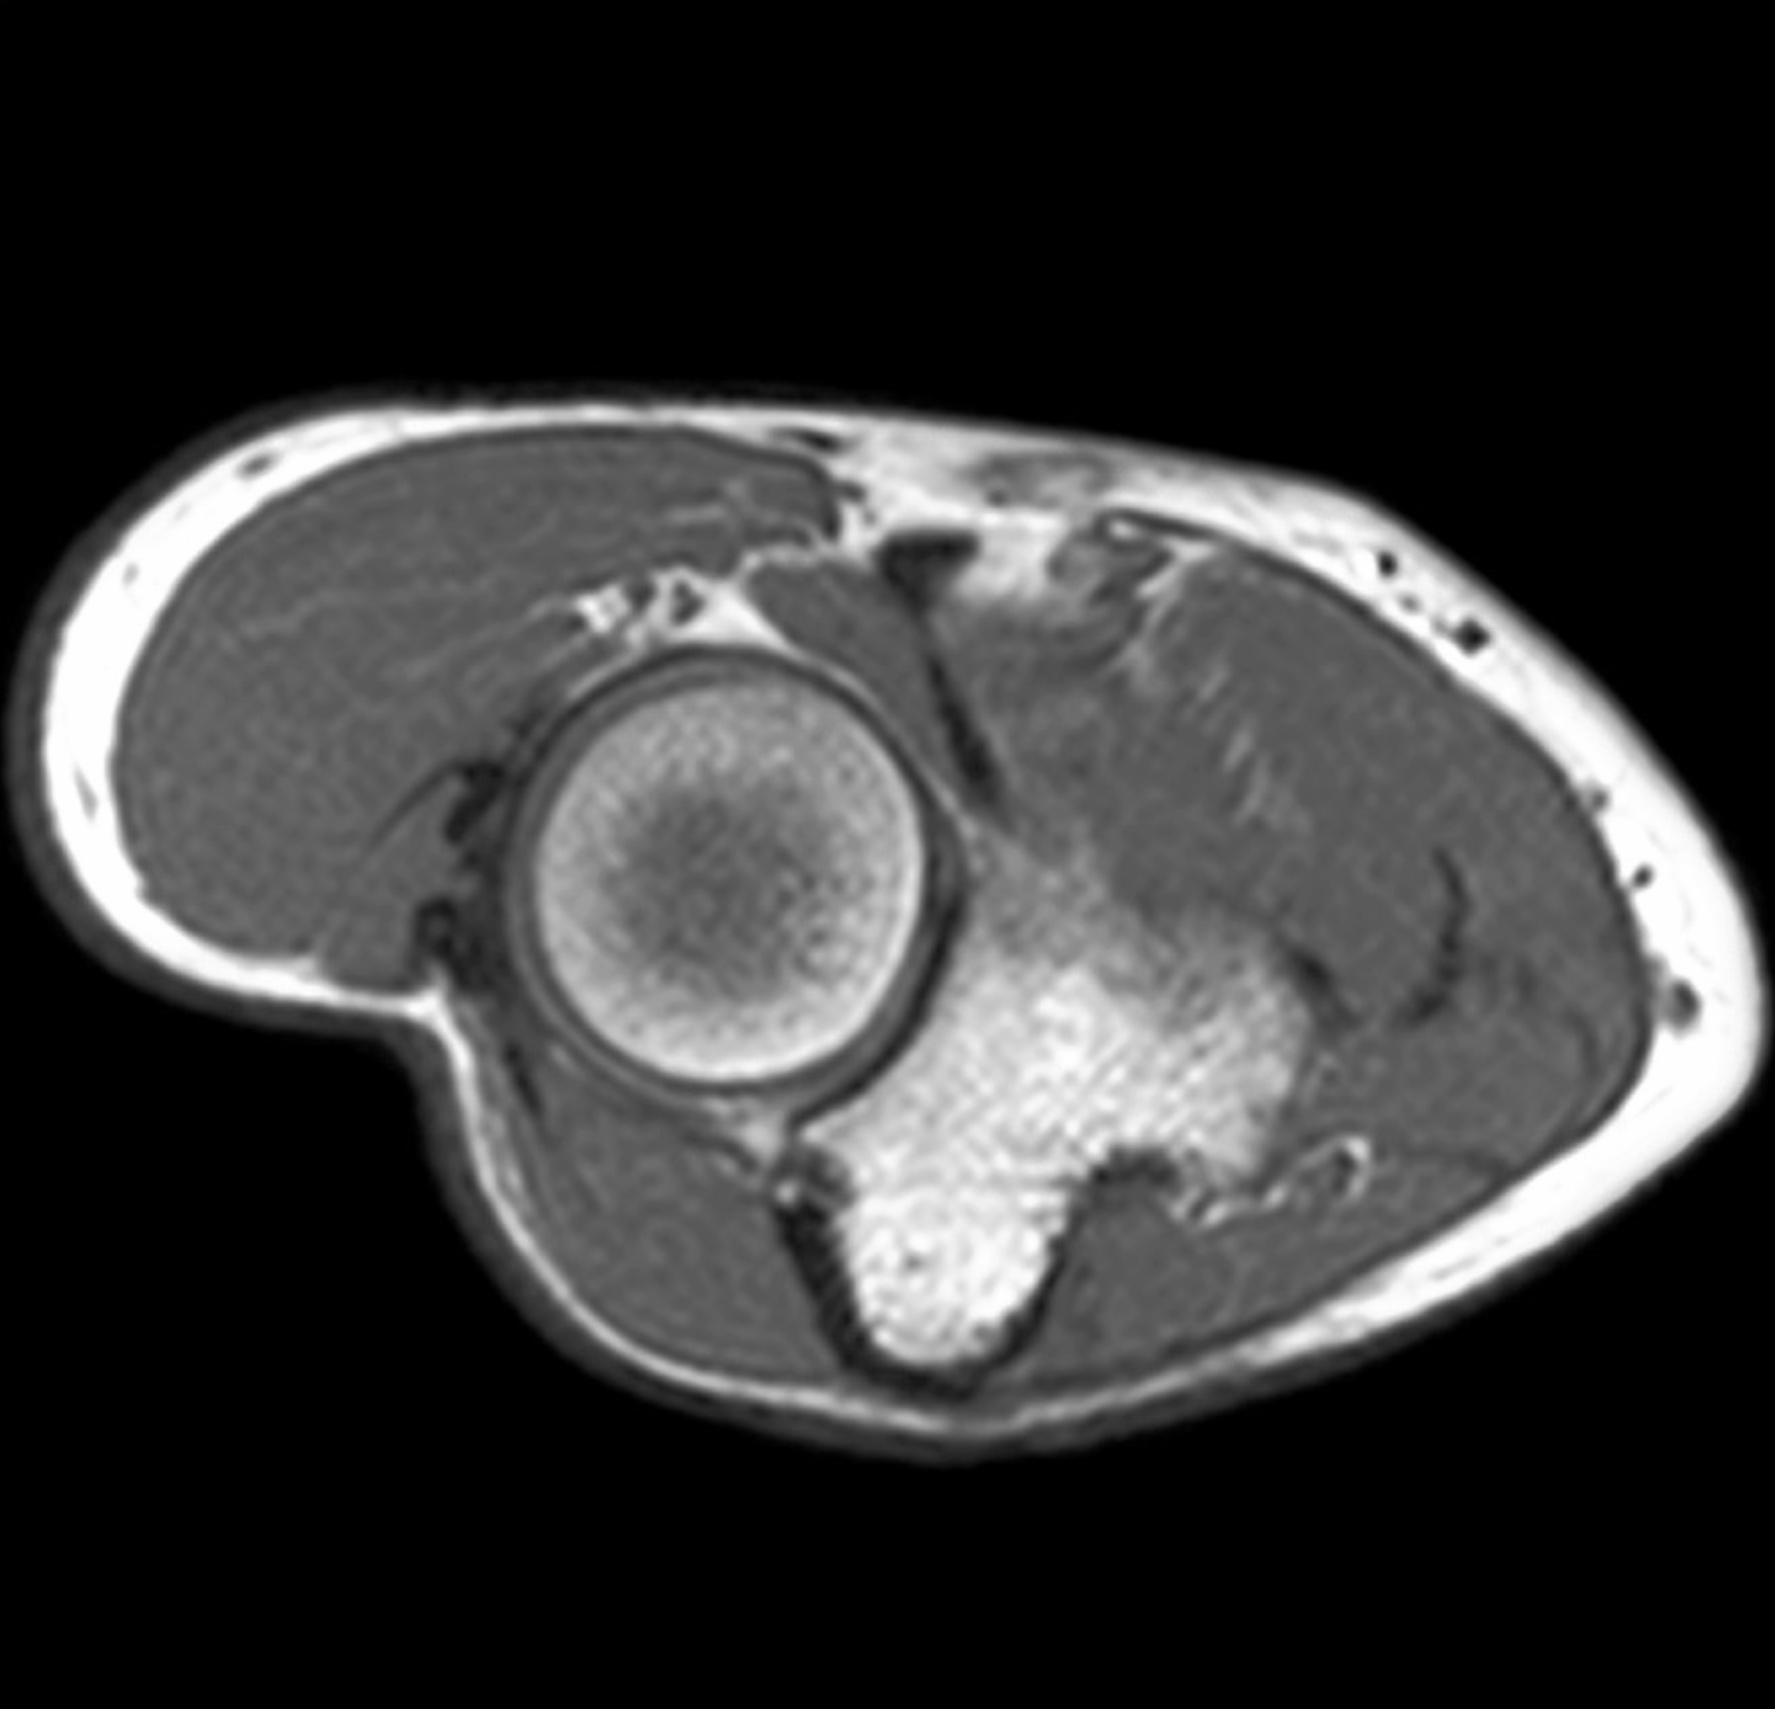

1. 34-yr-old male presents to the clinic with diminished sensation and paresthesia of the medial 1.5 digits. The patient just returned from a long distance cycling race. Describe the anatomy of Guyon’s canal. What major motor deficits would the patient present with for compression of Guyon’s canal? Include in your answer the named branches of the nerve involved and why the patient would be able to perceive sensation for the majority of the dorsum of the hand, but have diminished sensation for the nailbeds of the medial 1.5 digits. (G. Francis)